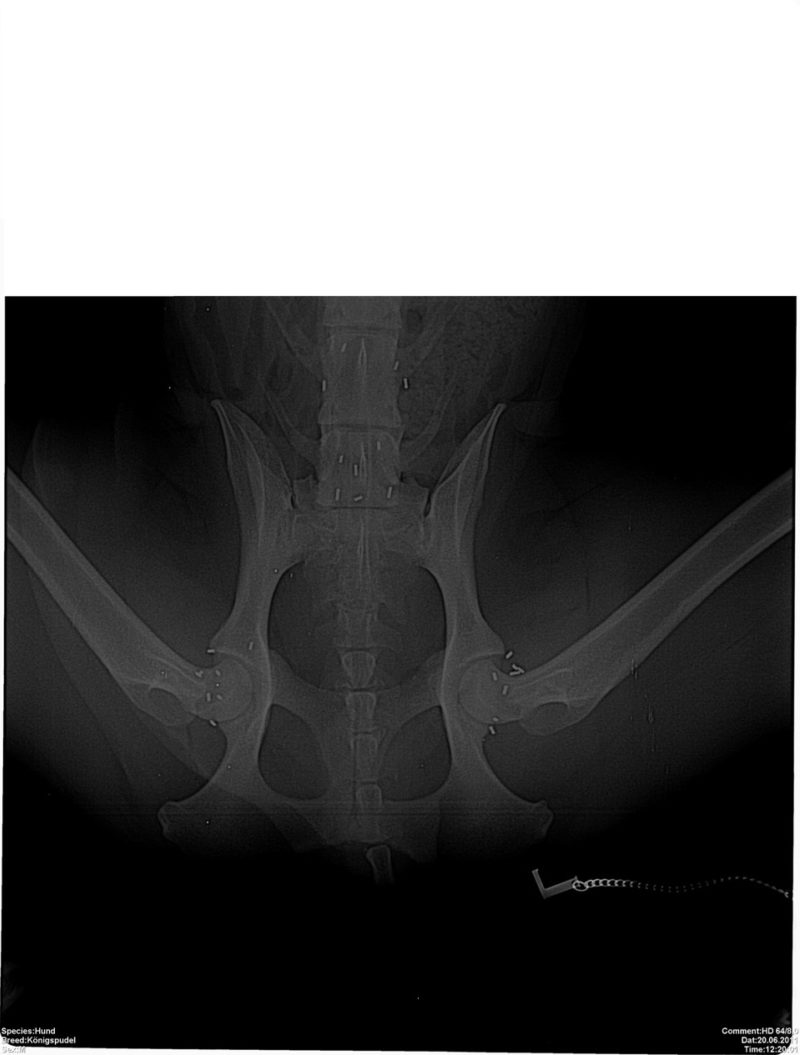

Bei einer eingehenden Lahmheitsuntersuchung fällt besonders der aufgezogene Rücken, sowohl im Stand als auch in der Bewegung, auf. Das für Hüft- und Beckenprobleme charakteristische „Po-Wackeln“ zeigte Tommy schon immer, allerdings hielten seine Besitzer das bisher nicht für ein Krankheitssymptom. Schließlich humpelte er ja bisher nicht. Neben weiteren Auffälligkeiten des Gangbildes ist vor allem der Schwung aus der Hinterhand und die Beweglichkeit der Wirbelsäule deutlich reduziert. Tommy legt sich beim Laufen regelrecht auf die Vorderhand. Beim Abtasten zeigt Tommy Schmerzen im Rücken sowie im Becken- und Hüftbereich. Auch die Triggerpunkte der Ellbogen reagieren auf beiden Seiten schon auf leichten Druck. Der Verdacht auf Arthrose in den Hüft-, Wirbel- und Ellbogengelenken wird  durch anschließende Röntgenbilder bestätigt. Was nun? Arthrose ist nicht heilbar. Also müsste Tommys Frauchen damit rechnen, ihn für den Rest seines Lebens immer wieder wegen Schmerzen behandeln zu lassen.

Bei der Goldimplantation werden dem Patienten nach einer sehr ausführlichen Untersuchung in Sedierung 1-3 Millimeter lange Golddrahtstückchen mittels einer Hohlnadel an Akupunkturpunkte und/oder spezielle lokale Punkte injiziert. Hauptanliegen der Goldimplantation ist die ganzheitliche Therapie des Körpers. Es wird also nicht z.B. eine einzelne Gelenkerkrankung behandelt, sondern die Bewegung als Einheit harmonisiert. Durch die entzündungslindernde Wirkung der Goldimplantate werden durch Entzündungen verursachte Schmerzen gelindert, die Durchblutung in diesem Gebiet verbessert und somit der Stoffwechsel und das Gangbild harmonisiert. Übrigens sind die Goldimplantate kein Hindernis für andere Behandlungsmethoden wie z.B. Akupunktur oder Chirurgie. Sie können sogar im Gegenteil oft sehr gut kombiniert werden. Bei punktgenauer Implantation durch spezialisierte Tierärzte stellt sich in der Regel recht bald eine Schmerzfreiheit oder zumindest –armut ein. Der Patient kann sich wieder besser bewegen und erlangt somit mehr Lebensqualität und Lebensfreude. Vorhandene Arthrosen werden nicht beseitigt, doch durch die Schmerztherapie können Schmerzmedikamente erheblich reduziert oder sogar abgesetzt werden. Da das Gold im Körper nicht abgebaut wird, hält diese Wirkung dauerhaft an.

Tommy bekommt in Narkose Goldimplantate an die zu seiner Problematik (Hüfte, Wirbelsäule und Ellbogen) passenden Akupunkturpunkte und zusätzlich ausgesuchte lokale Punkte. Er bewegt sich bereits wenige Tage nach der Goldimplantation (GI) deutlich lockerer. Schon nach wenigen Wochen sind die Triggerpunkte beim Abtasten nicht mehr sensibilisiert und Tommy spielt wieder fröhlich mit seinen Hundefreunden im Park. Diese Wirkung hält seit inzwischen sieben Jahren dauerhaft an, und Tommy hat viel Freude an seinem speziellen Senioren-Trainingsprogramm.